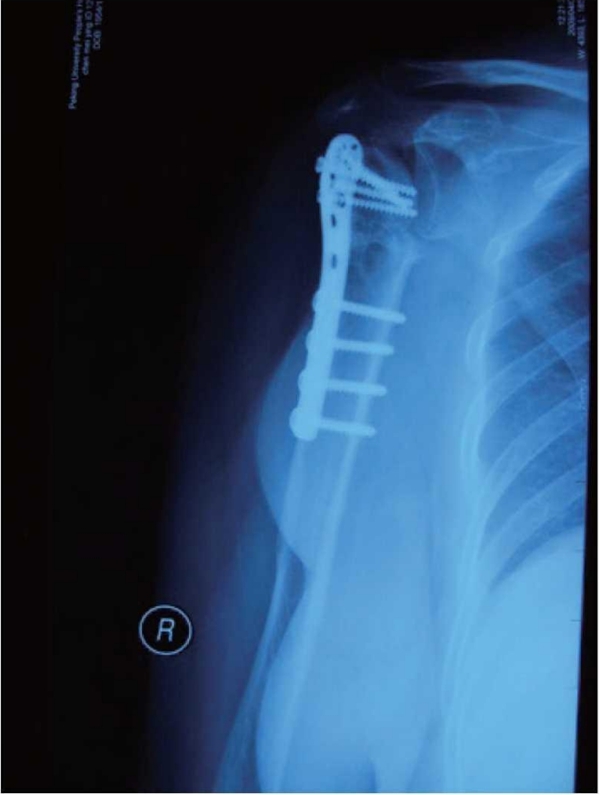

肱骨近端骨折内固定术后整体并发症发生率为30%。其中,常见的并发症主要有螺钉切出/穿透关节面、肱骨头内翻畸形、肱骨头缺血坏死、髓内钉移位、骨折不愈合、内固定断裂等(图1~3)。

图2 肱骨近端骨折术后肱骨头缺血性坏死、骨吸收